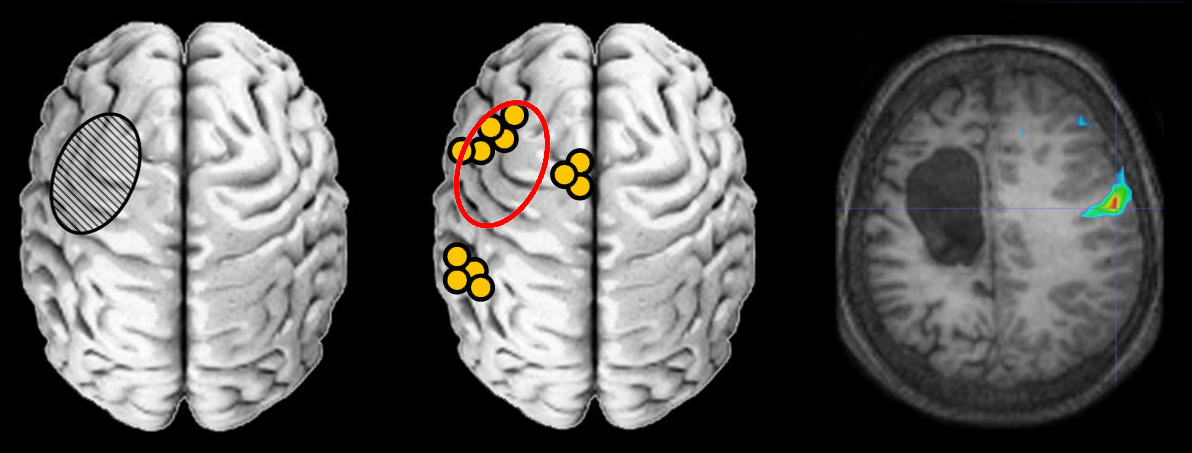

Neurosciences

Images et documents en rapport avec les articles

scenar7

Ancien logiciel : EduAnatomist et Neuropeda

Informations sur les images AnaPeda